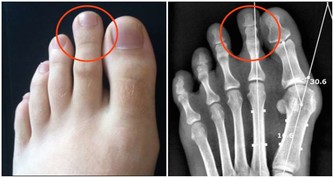

*****馬德龍病*****

酒精對身體的危害十分廣泛包括心腦血管、中樞神經、消化系統、肝膽脾胃等,我下面著重介紹一下不大多見,與酒密切相關一種病,馬德龍病。

馬德龍綜合徵是一種因長期飲酒,導致脂肪代謝紊亂,在皮下等部位對稱、過度堆積而形成一種病症。脂肪常會堆積在頭部、頸部、肩部以及腰部等部位,上下肢呈現近端肥胖、遠端細小,類似動漫“大力水手”的手臂外形。

患者常因堆積脂肪組織壓迫氣管、食管,出現呼吸困難和吞嚥受阻而就診。

發病特點,多為男性,有長年飲酒史,有的飲酒史長達20到30年之久,飲酒量大,每天飲酒在1.5斤至2斤。

隨著生活水平提高,飲酒者不斷增加,該病有增多趨勢。

目前馬德龍病治療,關鍵在於戒酒。

堆積脂肪可通過外科手術分期切除,或吸脂的方式進行清除,但這只是對症治療,不是根治之術,若患者不下決心徹底戒酒,復發只會是早晚的事。